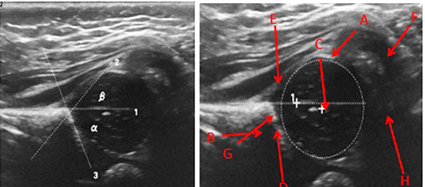

Realizamos una ecografía de ambas caderas a los niños menores de 3 meses, referidos a nuestro centro por padecer pie equino-varo no sindromático (parálisis cerebral infantil, artrogriposis y mielomeningocele), sospecha de DDC u otras patologías ortopédicas (Figura 1).

Seguimos la técnica descrita por Graf y la clasificación de Graf con 4 tipos de hallazgos sonográficos [7] (Figura 2). El equipo fue Logic E9 y transductor lineal de 14 MHz.

Figura 2. Ecografía de cadera pediátrica, a) ángulos a y b, 1. línea por el borde iliaco externo, que debe ser paralela al transductor, 2. línea por la punta del labrum y promontorio óseo, 3. línea que se traza por el techo acetabular osificado b) A. cápsula, B. techo acetabular osificado, C. cabeza femoral, D. Cartílago, E.) Labrum, F. Pliegue sinovial G. Punto de transición H. Borde osteocondral. Para calcular el porcentaje de cobertura femoral: Línea 1) línea paralela al iliaco y se traza circunferencia de cabeza femoral

Figura 2